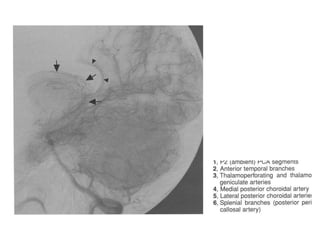

Segmentação da ACM

• M1 (esfenoidal): inicia na origem da ACM e termina em

uma curva de 90 graus (joelho), na junção dos

compartimentos esfenoidal e operculoinsular. É

subdivido em seguimento pré-bifurcação e pós-

bifurcação (proximal ao joelho).

• M2 (insular): começa no joelho, onde a ACM passa

sobre o límen da ínsula e termina no sulco circular da

ínsula, a maior ramificação acontece distalmente ao

joelho, terminam no topo do sulco circular, consistindo

em 6 a 8 artérias tronco principais.

• M3 (opercular): começa no sulco circular da ínsula e

termina na superfície do sulco lateral, estão

intimamente relacionados a superfície dos opérculos

frontoparietal e temporal. Se curvão 180 graus

formando alças.

• M4 (cortical): composto por ramos que se dirigem para

a convexidade lateral. M1 se bifurca em 6 a 8 artérias

tronco principais por hemisférios, cada tronco individual

(segmento M2 ou M3) origina tipicamente de um a

cinco ramos corticais (M4), divididos em grupos

anterior, intermediário e posterior.

As setas indicam M2 contornando o

sulco circular da ínsula. A seta maior o

ponto silviano posterior, emergência da

artéria angular.